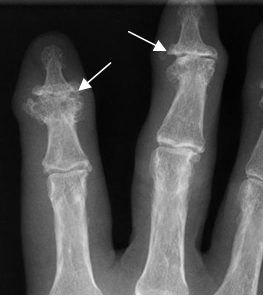

Fig 99. Artropatía degenerativa.

Rx AP. Cambios degenerativos de predominio distal, con formación de osteofitos y pérdida del espacio articular.